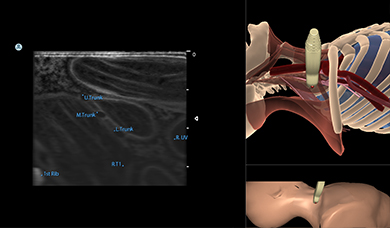

Simbionix Ultrasound Mentor is the answer to the growing need for ultrasound training among multiple medical specialties. This modular simulation platform enables easy manikin rotation (male, female, pediatric and interventional), and offers diverse applications for a range of specialties such as OB/GYN, Point-of-care Ultrasound (POCUS) and Echocardiography.

Ultrasound Mentor accelerates the development of basic to advanced technical and cognitive skills, by providing not only the probe manipulation training, but also a didactic environment enabling structured, self-guided learning including step-by-step instructions and educational aids such as 3D anatomical map and probe positioning assistant, all backed up with our progress monitoring tool MentorLearn.

Neck Module

Brachial Plexus Nerve Block Module

Central Line Ultrasound Module